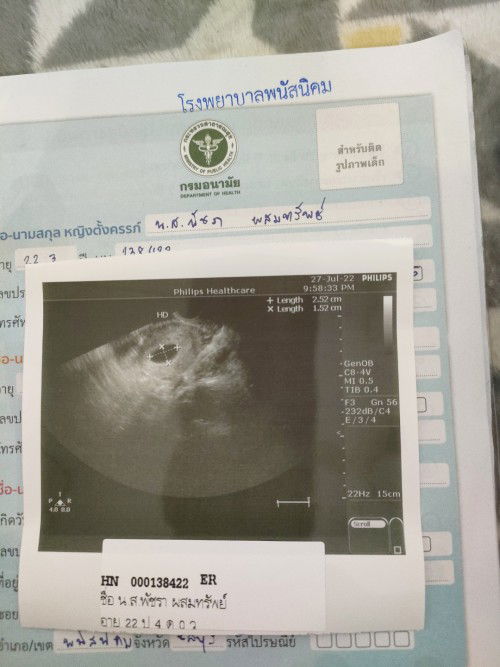

มีเลือดออกมา2วันไปหาหมอ หมออัลตร้าซาวด์+ตรวจภายใน ปากมดลูกปิดสนิท ถุงการตั้งครรภ์ยังอยู่ แต่ไม่เจอตั

มีเลือดออกมา2วันไปหาหมอ หมออัลตร้าซาวด์+ตรวจภายใน ปากมดลูกปิดสนิท ถุงการตั้งครรภ์ยังอยู่ แต่ไม่เจอตัวน้อง อีกนานไหมค่ะกว่าจะเจอน้อง